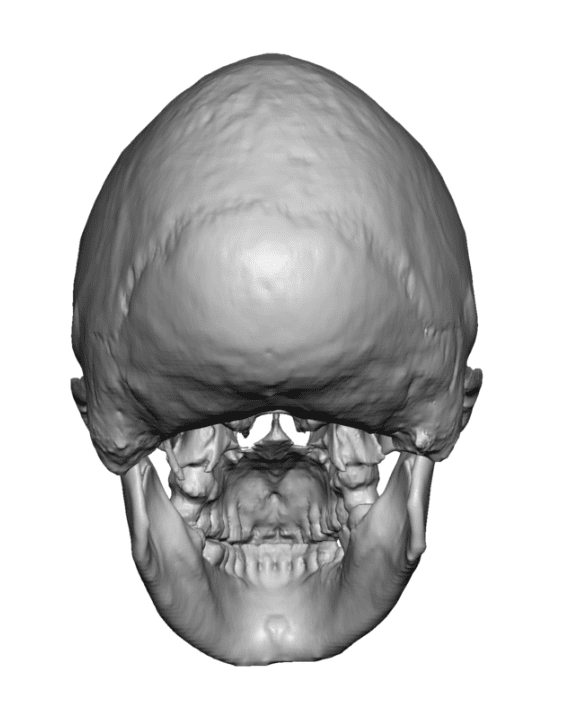

Male with congenital sagittal skull deformity with a long and narrow head.

Custom skull implant to widen the head from front to back with forehead and occipital skull bony reductions.